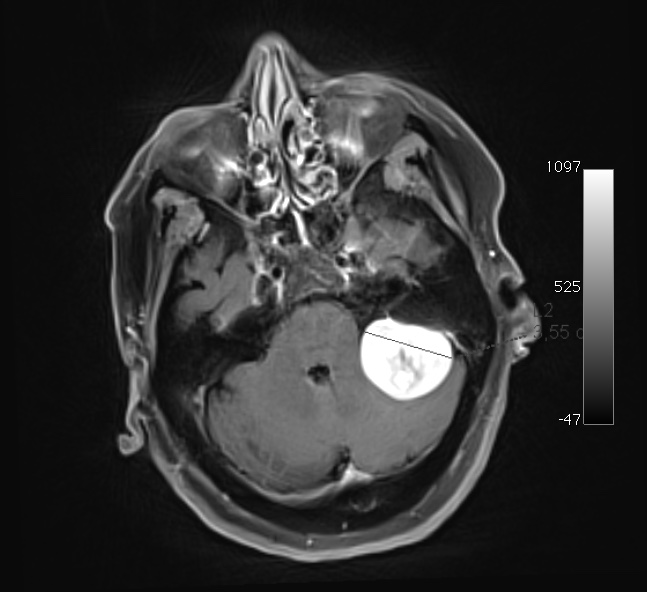

Η μαγνητική τομογραφία εγκεφάλου ανέδειξε εξεργασία στην περιοχή της αριστερής γεφυροπαρεγκεφαλιδικής γωνίας, ακτινολογικά συμβατή με μηνιγγίωμα.

Η ασθενής υπεβλήθη υπό γενική αναισθησία σε αριστερή υποινιακή κρανιοτομία και ολική αφαίρεση της βλάβης.

Η ιστολογική ταυτοποίηση ανέδειξε ευρήματα συμβατά με μηνιγγίωμα WHO I.